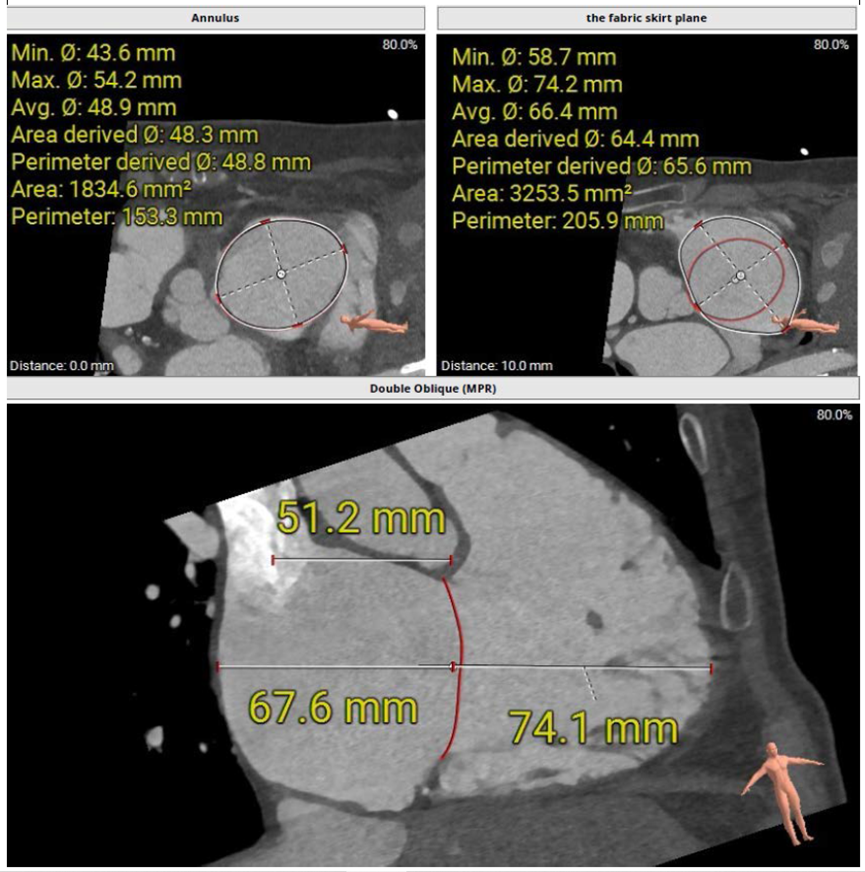

術前CT評估三尖瓣瓣環大小